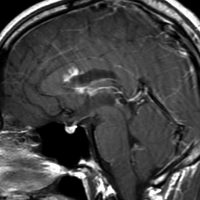

生検後2ヶ月,セカンドオピニオンのために受診された時の画像です。腫瘍が縮小傾向にあります。入院中に行われた何度かのCT被曝の影響で,germinomaの退縮が生じたのだと判断しました。

左はICE化学療法 (IFO/CDDP/VP-16)前,右は1コース終了後です。腫瘍は顕著に縮小してgerminomaとして普通の化学療法反応性を示します。また,松果体と下垂体には腫瘍はありません。

ICEを3コース行なって腫瘍は完全消失して,前頭葉浮腫も消えました。その後に,全脳照射 25.2Gy/14分割を加えました。無症状で復職することができました。